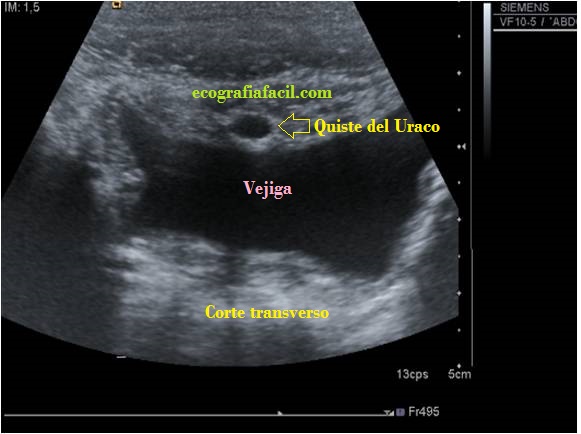

Nos quedamos con el número 2 y te lo presento en imágenes…mira:

La paciente acude por molestias abdominales, la prueba discurre normalmente, pero al pasar en línea media antes de llegar a la vejiga, una imagen pequeña, ovalada, medial, anecoica ocupa la parte superior de la vejiga. Se demuestra en la primera imagen, se corrobora con la imagen 2, o corte longitudinal donde se demuestra clarísimamente su situación anatómica con respecto a la vejiga y a los tejidos circundantes.

El doppler no aportó información adicional, la radióloga informó «Quiste del Uraco». Estoy seguro que si alguna vez lo ves, te vas a acordar de este Post…